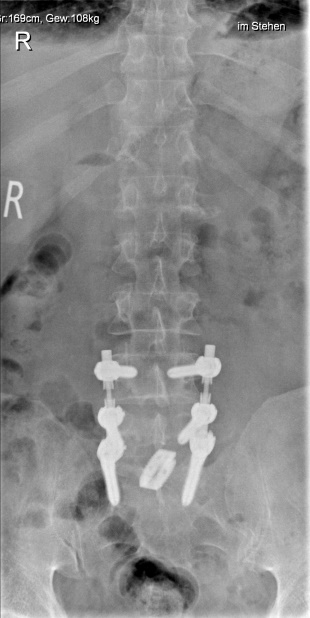

Beispiel Dynamische Neutralisation/Kombinationsverfahren

Bei rein degenerativer Erkrankung einer Bandscheibe ohne Mitbeteiligung der Facettengelenke und ohne krankhafte Veränderung der Nachbarwirbel ist die dynamische Neutralisation des Segmentes möglich. Kombinationsverfahren mit Versteifung und dynamischer Neutralisation können gegebenenfalls sinnvoll sein.